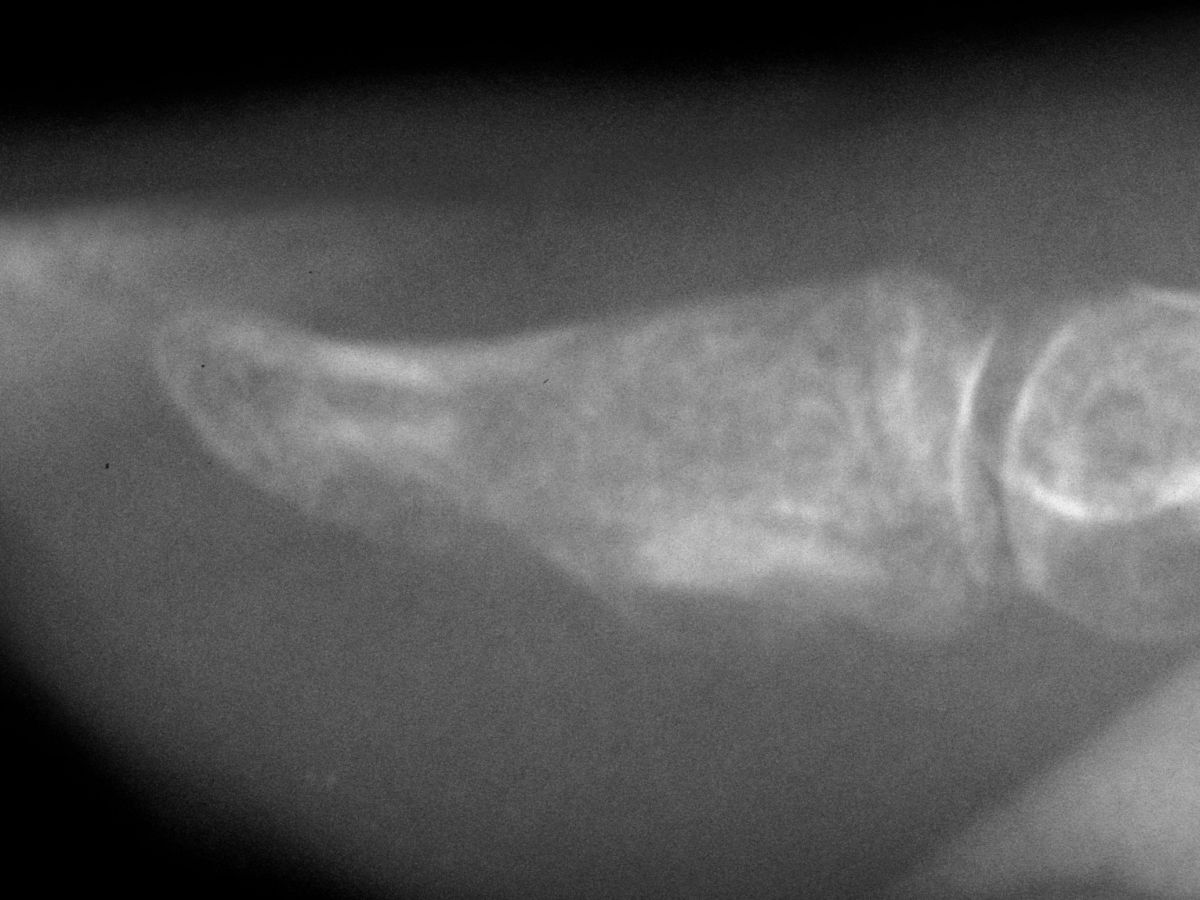

| Case 1. This patient presented with pain with thumb pinch and a sense of fullness in the thumb pulp. Plain radiographs demonstrate an expansile, geographic, radiolucent, juxtaarticular intraosseous mass, typical for an enchondroma. There is circumferential cortical thinning and possible cortical breaks. |